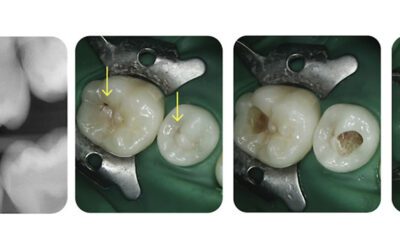

A recent case study on Dental Decay

We recently saw this 15 year old patient for a check-up and identified possible signs of tooth decay. Following an X-Ray, it was clear that there was significant tooth decay and caries needing...